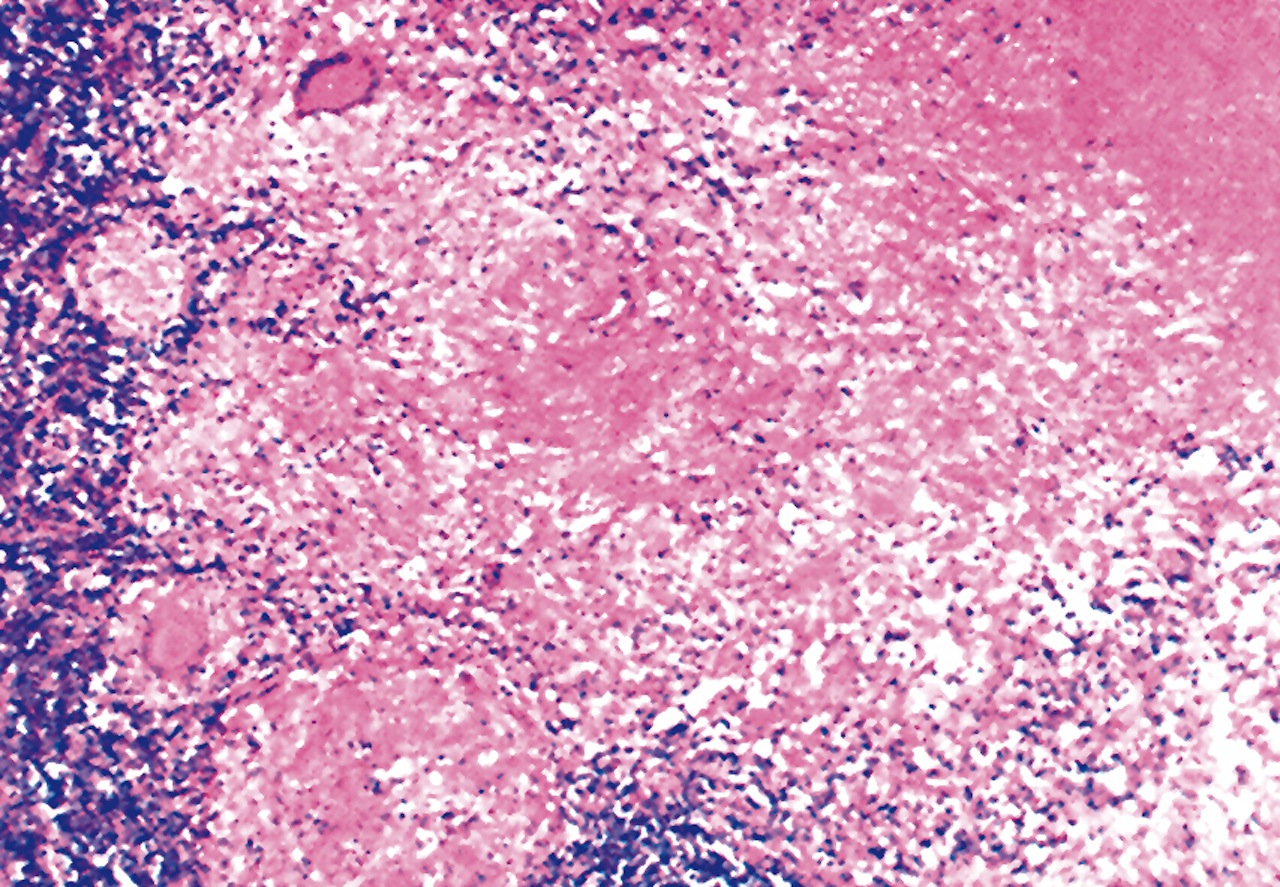

Microscopic (histologic) description

- Focal nodal effacement by multiple coalescing intranodal clusters of small blood vessels, lined by epithelioid endothelial cells with pale cytoplasm

- May have focal nuclear atypia

- Interstitium contains abundant eosinophilic to amphophilic, amorphous or granular material containing aggregates of bacteria (highlighted by Warthin-Starry stain)

- Also neutrophils

Microscopic (histologic) images

AFIP images

- Post vaccination bacille Calmette-Guerin infection occurs in 1% of infants, although swelling usually subsides (Braz J Med Biol Res 2004;37:697)BACILLARY ANGIOMATOSIS Left: Proliferated blood vessels are separated by abundant eosinophilic, vaguely fibrillary material. Some neutrophils are also seen. Right: Barely canalized blood vessels separated by eosinophilic interstitial materials in the absence of neutrophils.